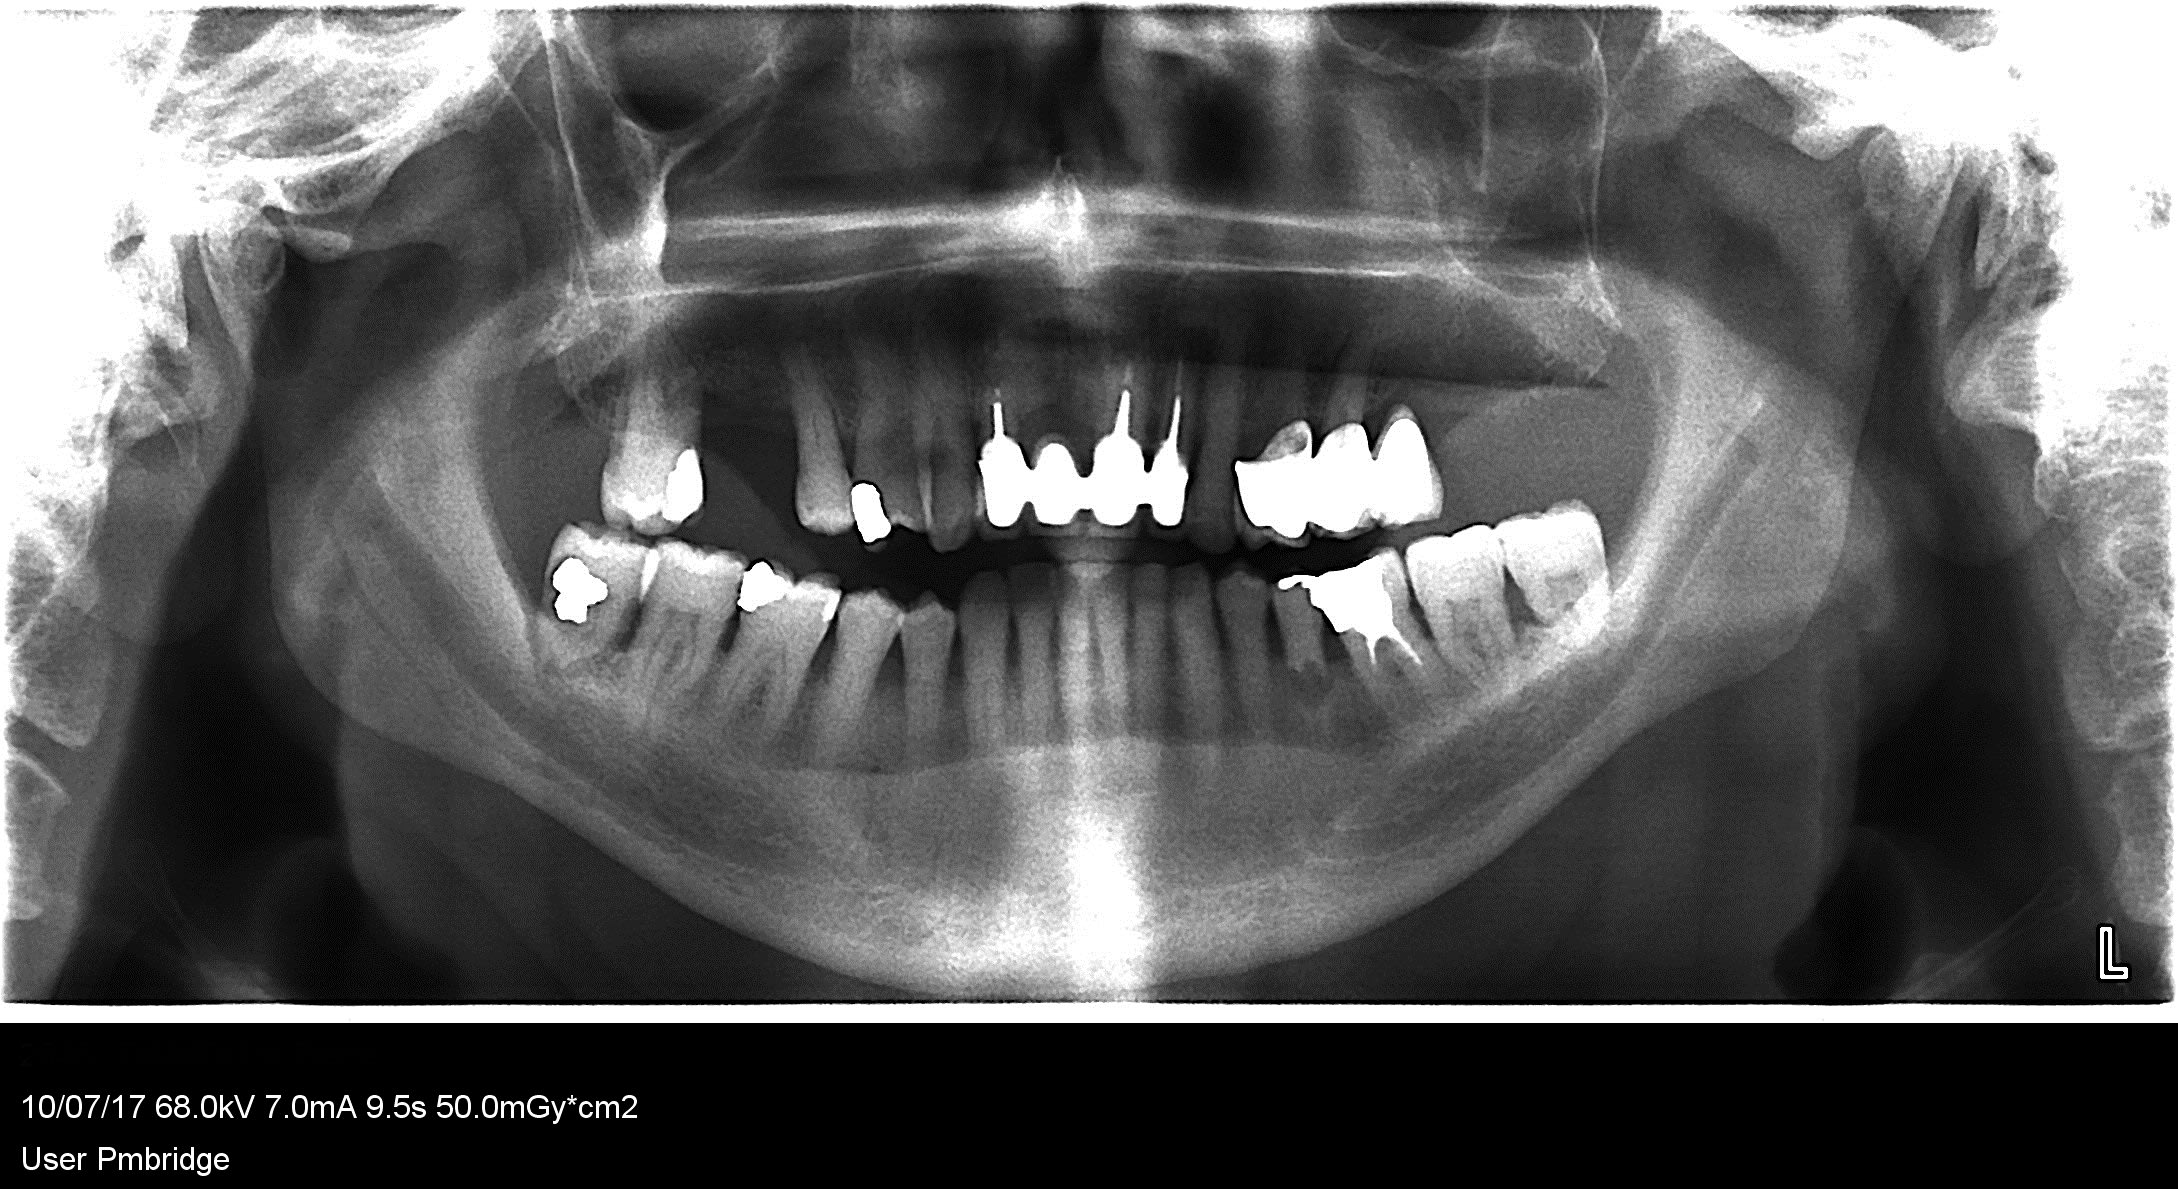

autres radios

pano 2017